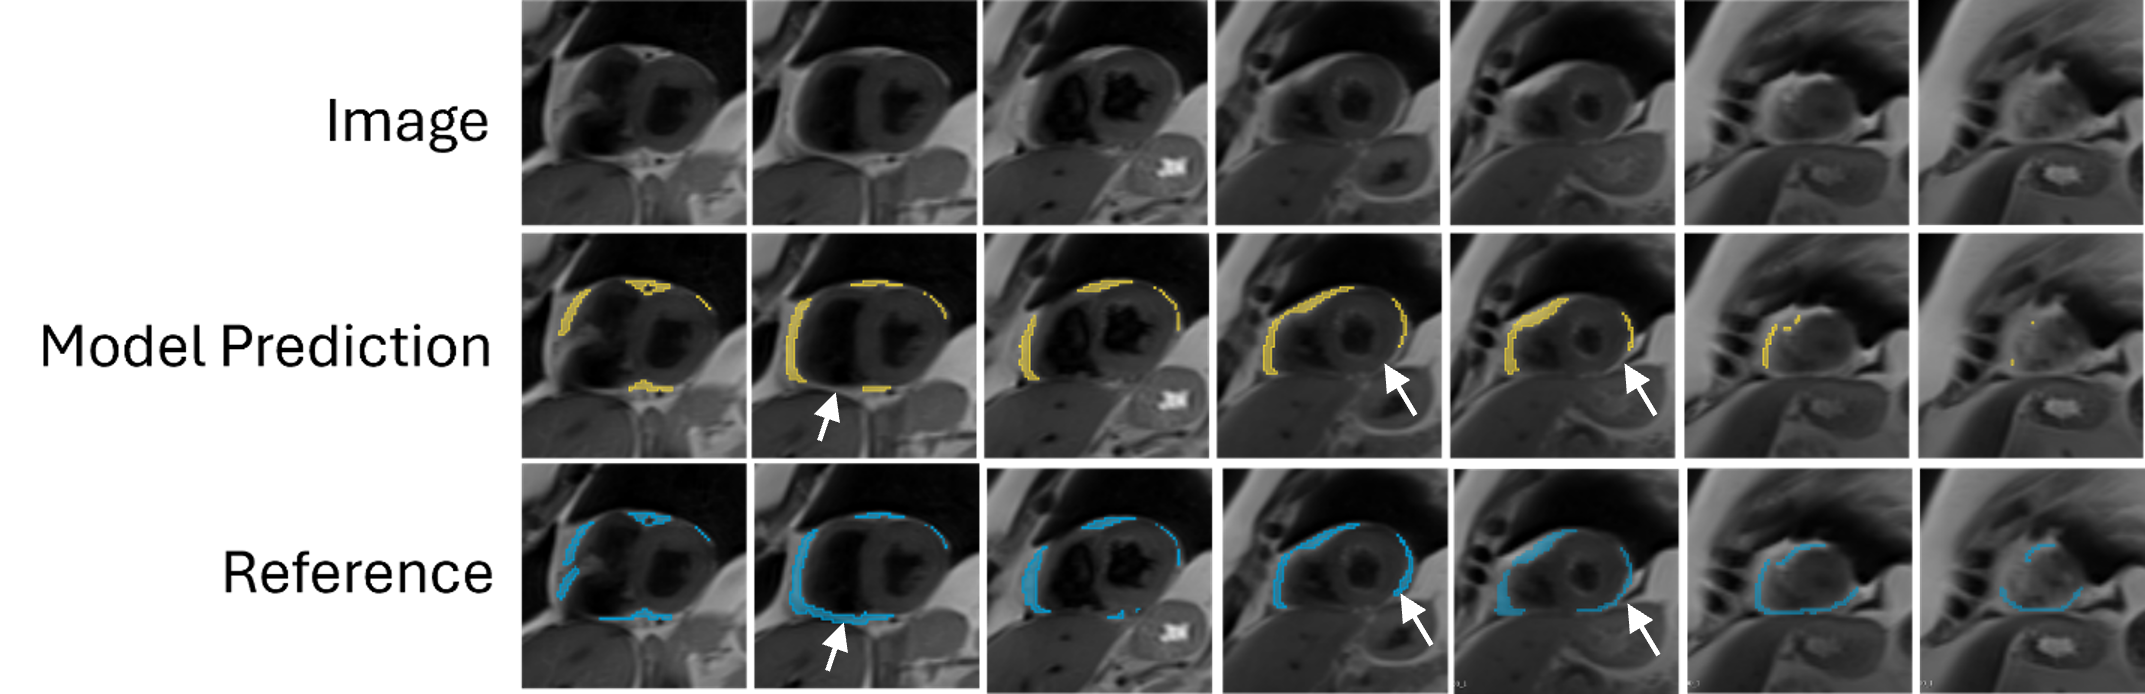

Figure 3: Representative examination illustrating the model prediction and reference segmentations across slices of the cardiac base to apex. The model underestimates the EAT on the inferior surface of the heart and around the apex, as indicated with white arrows..png)